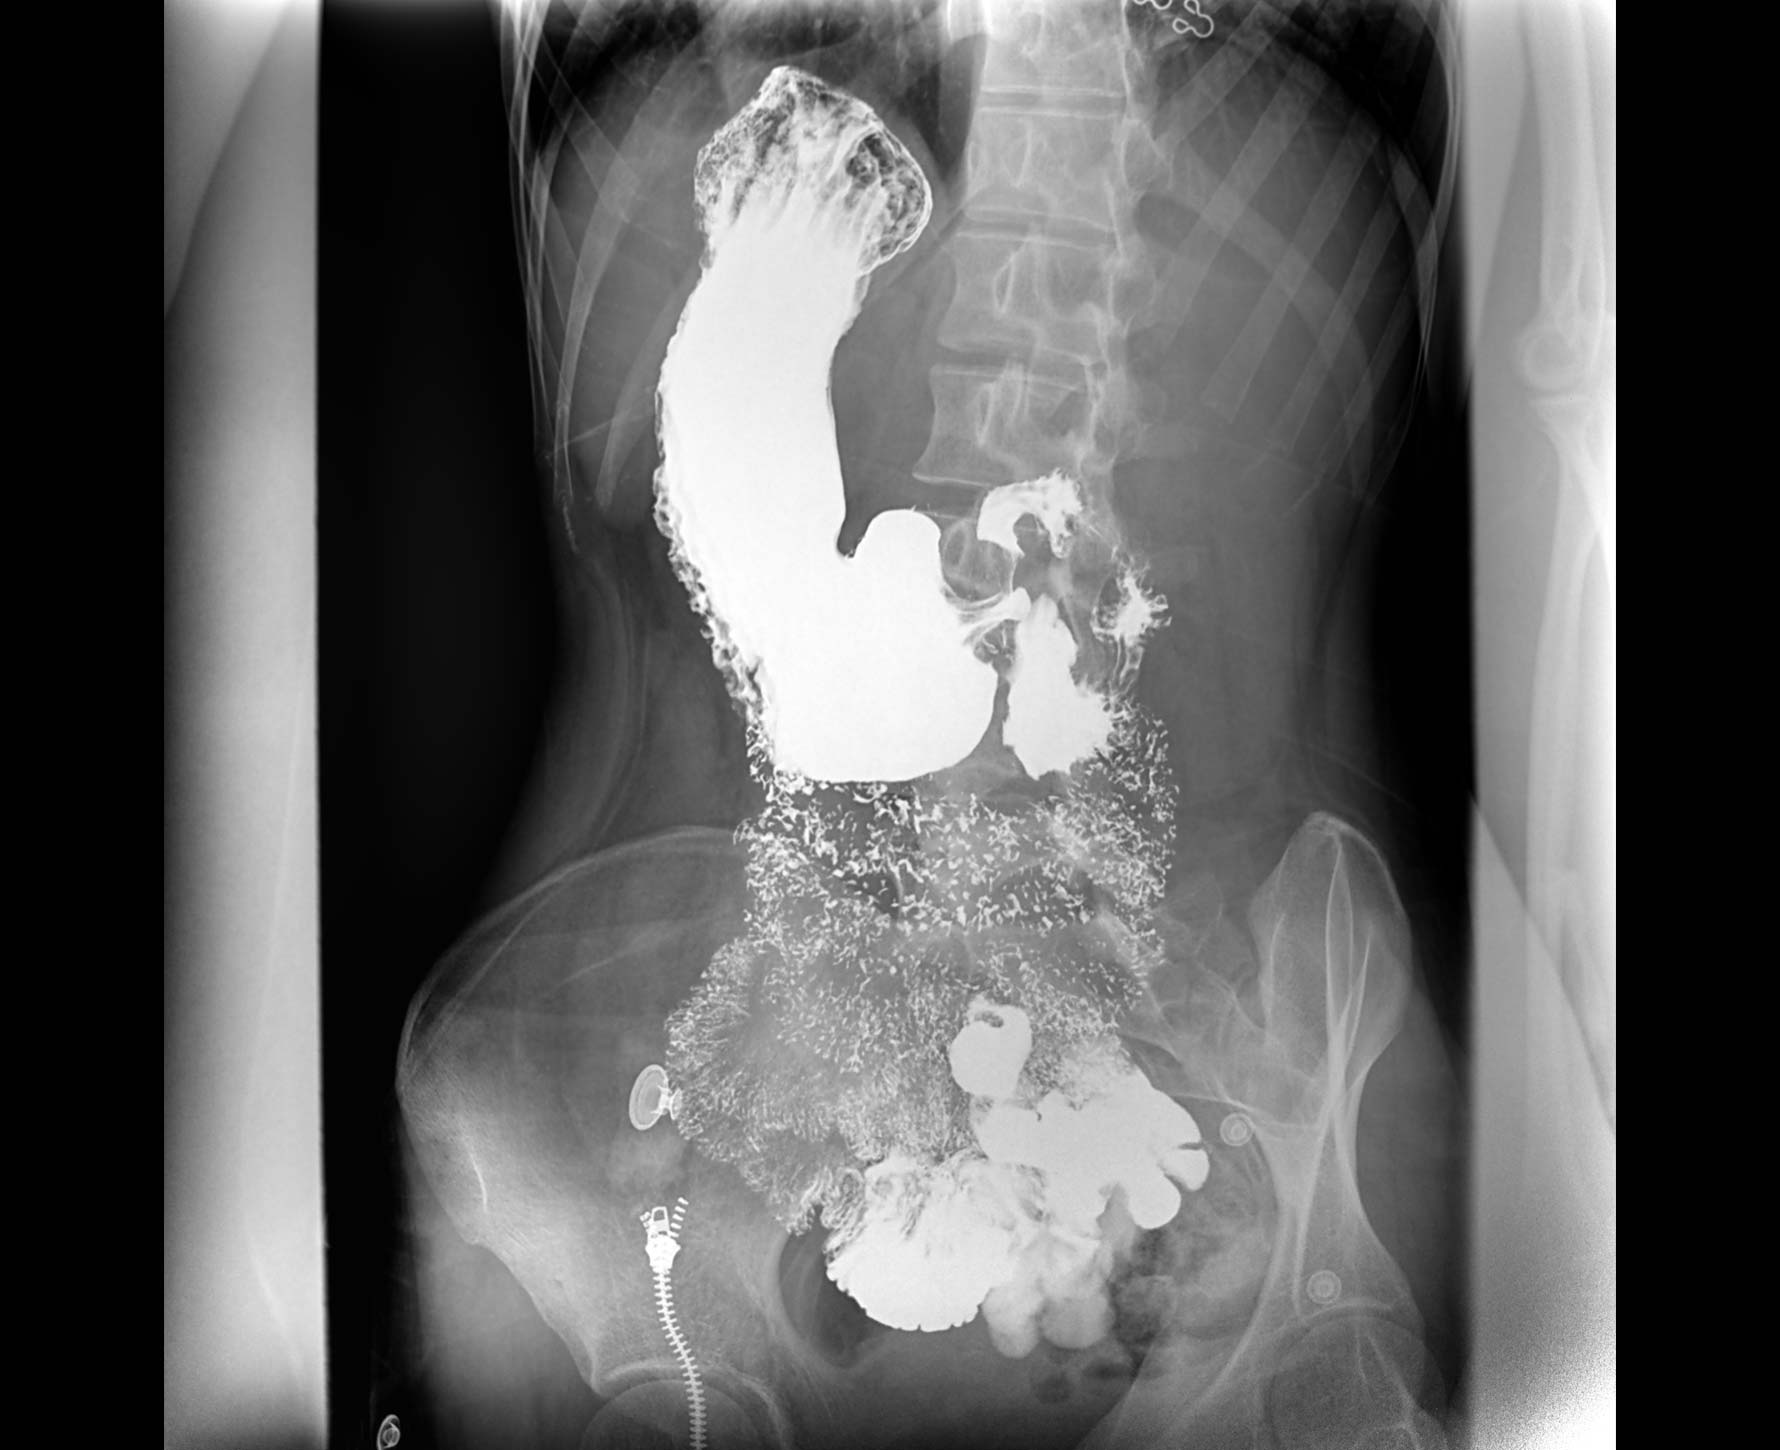

適用于各種普通

及特殊胃腸造影檢查

對胃腸造影檢查影像實時保存,多次回放以便確定病灶部位,患者確診好幫手,減少漏診。